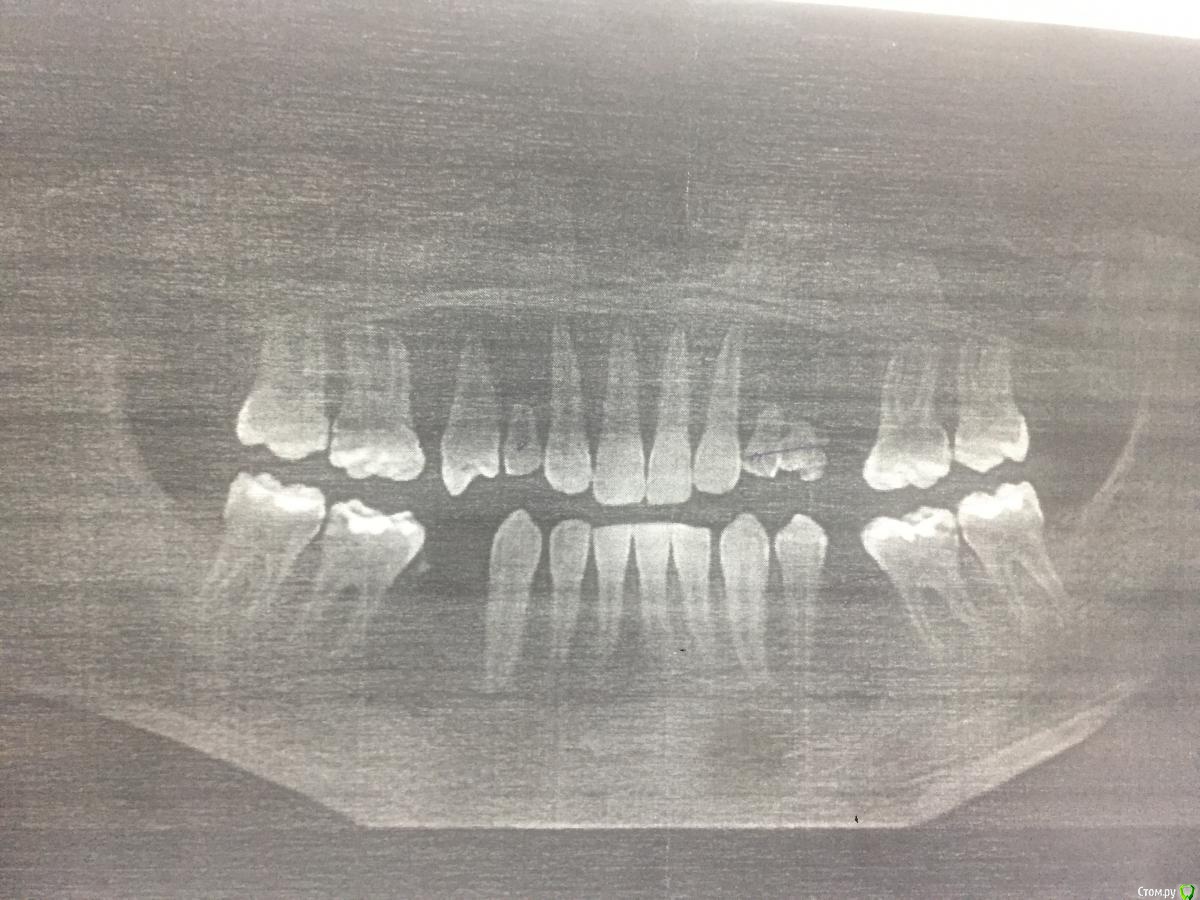

AAbdymomunov Опубликовано 17 июля, 2019 Поделиться Опубликовано 17 июля, 2019 Нужна консультация 15 лет Ссылка на комментарий

Bier Опубликовано 18 июля, 2019 Поделиться Опубликовано 18 июля, 2019 начинайте ортодонтию, затем имплантация. Кейс простой. Ссылка на комментарий